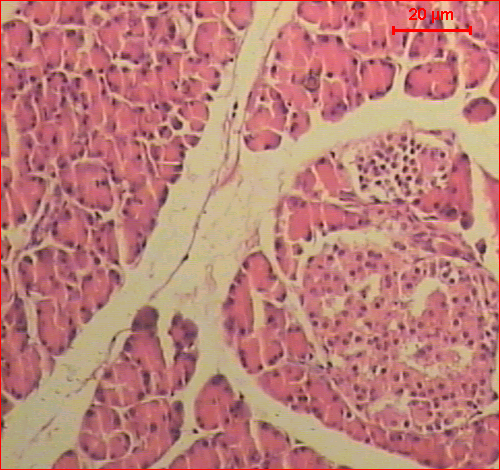

Sections of the control pancreas of rats showed the exocrine component of the pancreas that consisted of closely packed acini. The interlobular duct, surrounded with the supporting tissue. The endocrine tissue of the pancreas, islets of Langerhans, scattered throughout the exocrine tissue (fig. 2─A). Microscopic investigation of sections of pancreas of rats treated with 100 mg/kg b.w. of ethyl acetate or methanol extracts of Conyza dioscoridis for 21 days showed acinar cells and islets that were seen to be normal. The islets were present with volume and the numbers of pancreatic β-cell appeared more or less as control one (fig. 2─B, C).

The histopathological examination of pancreatic tissues revealed a decrease in pancreatic islet number and size, atrophy, and connective tissue invasion in the parenchyma of the pancreas islet was detected. On the other hand, a reduction in pancreatic β-cell numbers compared to the control group (fig. 2─D).

On treatment with 100 mg/kg b.w. doses of ethyl acetate extract of Conyza dioscoridis showed dramatic decrease in all abnormal histological changes as compared to the diabetic group (fig. 2─E). Significantly, lesser histological changes occurred in the methanol extract of Conyza dioscoridis treated group (fig. 2─F).

Fig. 2: Sections of the pancreas of A) control rat shows the exocrine component of the pancreas that consisted of closely packed acini. The interlobular duct, surrounded with the supporting tissue. The endocrine tissue of the pancreas, islets of Langerhans, scattered throughout the exocrine tissue, B, C) rats treated with ethyl acetate and methanol extracts of Conyza dioscoridis show the normal structure of the exocrine and endocrine pancreas, D) diabetic rat showed the acinar cells around the islets though seem to be in normal proportion does not look classical. A decrease in pancreatic islet number and size, atrophy, and connective tissue invasion in the parenchyma of pancreas islet was detected, E) diabetic rats treated with ethyl acetate extract of Conyza dioscoridis shows acinar cells and islets that were seen more or less like normal, and F) diabetic rats treated with methanol extract of Conyza dioscoridis shows lesser histological changes (H&E, Scale bar: 20 µm)